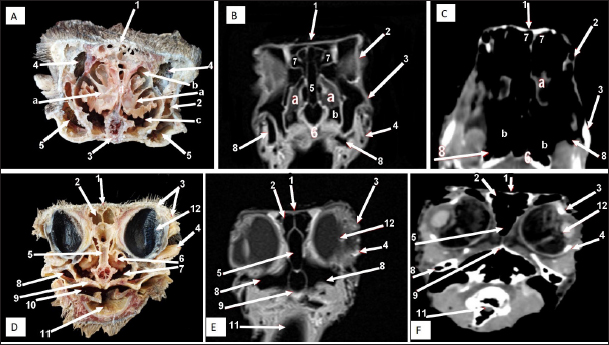

Fig. 3. Sagittal cross section of the adult ostrich head—level 2. A) Photograph of a paramedian sagittal anatomical section (medial view). B) MRI and C) computed tomography images showing: 1- Os premaxillare, 2- Os dentale, 3- Os nasale, 4- Processus. frontalis, 5- Frontal sinus, 6- Os parietale, 7- Os temporalis, 8-Palate, 9- Oral cavity, 10- Tongue, a- Rostral nasal concha, b- Middle nasal concha, c- Caudal nasal concha, d- Dorsal nasal meatus, e- Middle nasal meatus, f- Ventral nasal meatus, g- Infraorbital sinus, h- Orbit containing eye ball, i- Choanal opening and j-Cranial cavity.

Fig. 4. Sagittal cross section of the adult ostrich head—level 3. A) Photograph of a paramedian sagittal anatomical section (medial view). B) MRI and C) computed tomography images showing: 1- Os premaxillare, 2- Os nasale, 3- Frontal sinus, 4- Processus.frontalis, 5- Cerebral hemisphere, 6- Os frontalis, 7- Os dentale, 8- Oral cavity, 9- Tongue, a- Middle nasal concha (rostral part), b- Middle nasal concha (caudal part), c- Ventral nasal meatus and d- Vomer.

Fig. 5. Sagittal cross section of the adult ostrich head—level 4. A) Photograph of paramedian sagittal anatomical section (medial view). B) MRI and C) computed tomography images showing: a- Rostral nasal concha, b- Middle nasal concha, c- Caudal nasal concha, d- Middle nasal meatus, e- Ventral nasal meatus, f- Infraorbital sinus, g- Orbit containing eye ball, h- Frontal sinus and i- Os temporalis.

The nasal conchae exhibited in the MRI images as bright (high or hyperintense signal intensity) to gray (low or hypointense signal intensity) structures that could be divided into three parts: rostral, middle, and caudal conchae, which correlated to the morphological examinations. In contrast, the nasal conchae could not be recognized clearly on CT images compared to those obtained after MRI (Figs. 25 B and C). The paranasal sinuses with other structures could be identified using both CT and MRI. The nasal septum and paranasal sinuses revealed a white bone border (high signal intensity), soft tissue was grey (low-to-intermediate signal intensity), and they contained black gas, so both the CT and MRI scans showed little signal intensity (Figs. 15B and C and 79B, C, E, F).

Two featherless oval nostrils were found on either side of the premaxilla and covered by a characteristic operculum at the entrance. The upper beak’s dorsal ridge (culmen) was located between both nostrils (Fig. 1A and B). The nasal cavity was cone-shaped, extending to reach the choanae. Dorsolateral bony boundaries of the nasal cavity are the frontal process of the premaxilla, nasal, and dorsal horizontal plate of ethmoidal and nasal bone’s lateral process, while the ventral boundary created by the maxillary and palatine processes of the premaxilla, maxilla, and rostral part of the pterygoid and vomer bones. The vomer bone was pneumatic. The nasal septum divides the nasal cavity into two halves and consists of caudal bony and rostral cartilaginous parts (Fig. 2).

There are three types of nasal conchae: rostral, middle, and caudal (Figs. 35). The rostral nasal concha extended to reach the middle third of the nasal cavity (Fig. 3), and it was partially visible through the nostrils (Fig. 1B). The cross-section showed a T-shaped projection linked to the nasal cavity’s lateral wall, forming dorsal and ventral recesses. The rostral concha extends caudally beneath the rostral section of the middle nasal concha, forming the middle nasal meatus. At the floor of the nasal cavity, there is a feature mucous membrane fold connecting the rostral concha to the nasal septum (Fig. 6).

The middle nasal concha was more prominent than the rostral concha. It was situated on the caudo-dorsally to rostral one and resembled a coiled or bulla-shaped structure. The middle nasal concha was located in the middle of the nasal cavity, between the dorsal and middle nasal meatus (Figs. 3,4,5,6D, and 7A).

The caudal nasal concha is the smallest triangular one. In cross-section, it appeared scroll-like, attached rostrally to the middle one, making it difficult to differentiate between them. While caudally, the ventral nasal meatus was connected to the infraorbital sinus and the oropharyngeal cavity by two slits (or holes) in the palate called choanae.

Paranasal sinuses

Two paranasal sinuses were detected, triangular-shaped infraorbital and two identical frontal sinuses as the infraorbital paranasal sinus was identified as a triangular chamber rostroventral to the orbit (Figs. 3 and 8A), while the frontal paranasal sinuses were positioned dorsally, separating the cranial and nasal cavities. There were two frontal sinuses, one on the right and one on the left, separated by a bone septum in the center. The frontal sinuses were found between the frontal and nasal bones, dorsally and laterally, between the lacrimal and vertical plates of the ethmoidal bone (Figs. 2, 3, 4, 7D, 8, and 9A). All last structures were compared and verified by CT and MRI, to guarantee precise identification and labeling; the anatomical section structures for each cross-section level were matched to their corresponding MRI and CT images. In CT images, the bones appeared white (high CT density), the gaseous parts were black (the lowest attenuation), and the soft tissue was grey (low-to-intermediate CT density). In MR images, bones appeared white (high signal intensity), the gaseous parts were black (no signal intensity), and the soft tissue was grey (low-to-intermediate signal intensity).